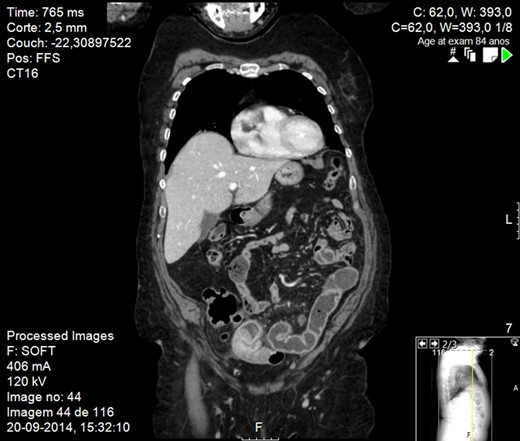

Abdominal X-ray revealed small bowel distension with multiple hydroaeric levels. Abdominal computed tomography (CT) scan (Figs 1 and 2) demonstrated distension of the small bowel due to an intraluminal mural mass with 4 cm in diameter, being the intestine collapsed distal to it. There was no evidence of other metastatic disease, including the liver.

CT scan image showing small bowel obstruction due to polypoid intraluminal masses.